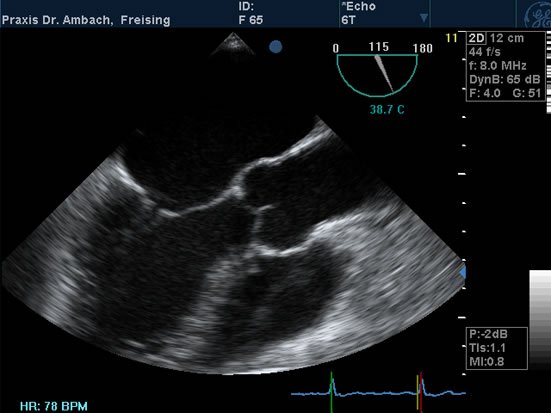

Echokardiographie

TEE - 1